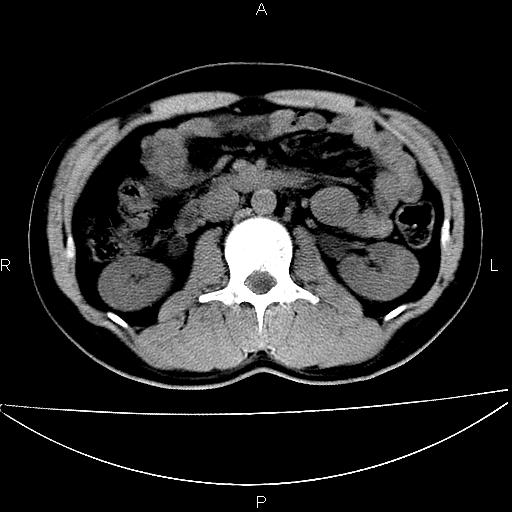

男 25岁 自述 尿频尿急,排尿困难20多天.无腰痛, b超说左肾盂轻度积水,左输尿管上端扩张.未见结石影. ct我看双侧肾盂轻度积水,双输尿管上端都扩张,大家看看能看见结石吗?

双肾轻度积水,双侧输尿管上段扩张(原因待查)。

双输尿管扩张下端未见高密度结石和输尿管晕轮征,不好说是结石.增强后如何?

双肾轻度积水,未见明确结石,薄层对结石检出率较高。

双肾盂及双输尿上段轻度积水,双输尿管未见明显结石影。